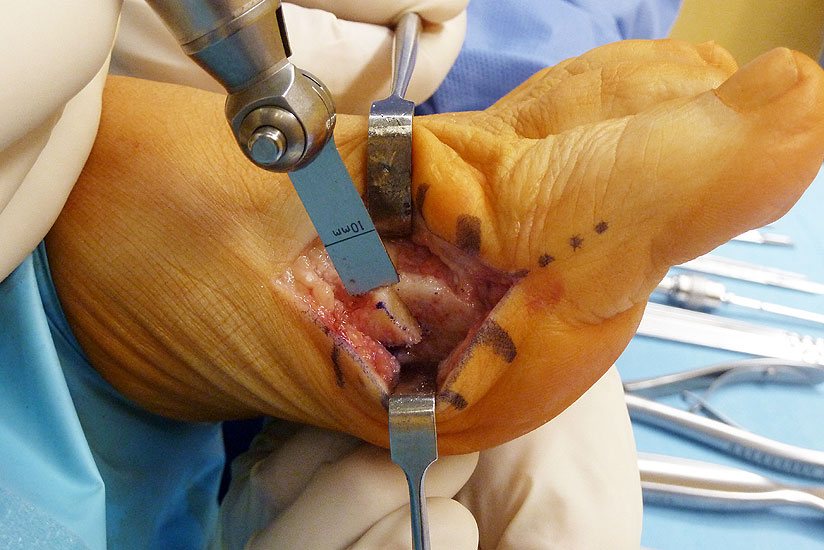

Abbildung 2

Allgemeines Fußinstrumentarium mit Pinzetten, Skalpell(en), Klemmchen, Luer, kleiner Meisel, Seidenschneider, Zange, kleine Langenbeckhaken und Hohmann-Hebel, Präparierschere, kleines Raspatorium und McGlamry Elevator (Abbildung 2)